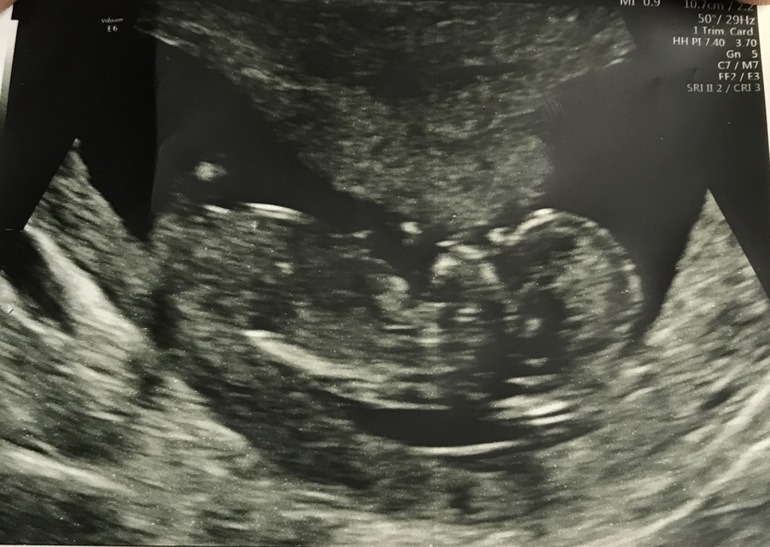

Узи 12,5 недель.

Сегодня была на скрининге, врач срок подтвердил, 11 акушерских, но полноценный скрининг, решил делать через две недели 27-го. Сейчас сердечко послушал, фотку дал, наш малышок на спинке лежит, носик, ротик и даже пуповинку видно. Я такая счасливая!!! ...